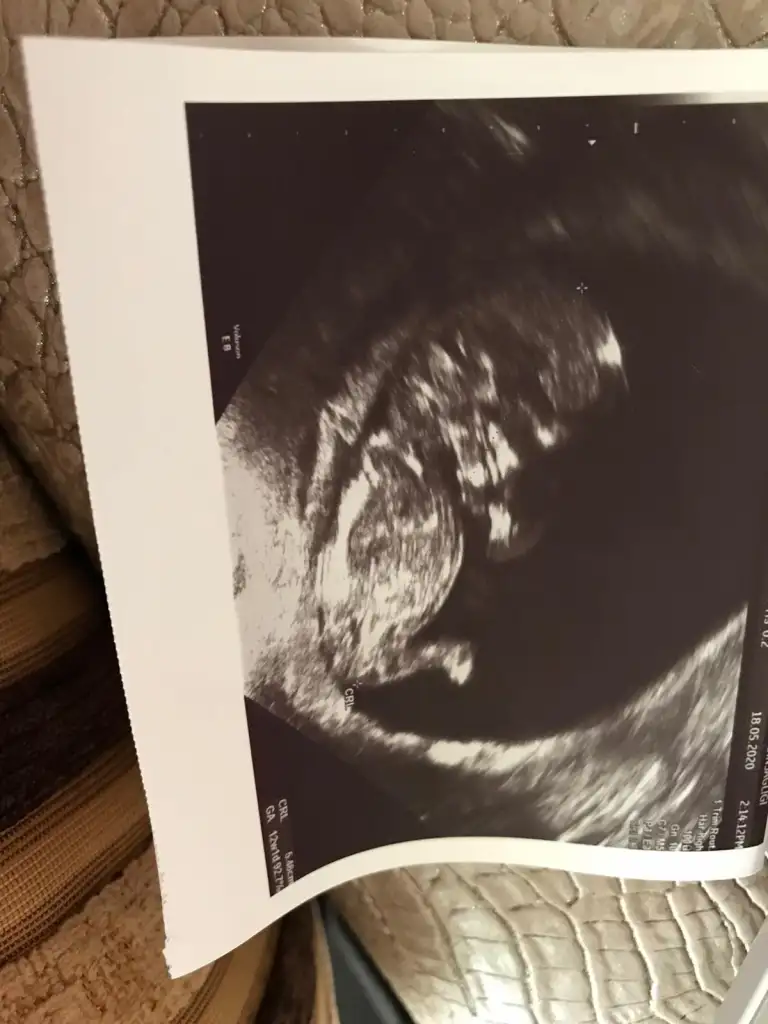

kızlar merhaba 12+1 olmuşuz bugün 3 kere ultrasona girdik fakat ense kalınlığı ölçülemedi çünkü benim bebiş o kadar çikolataya rağmen uygun pozisyona dönmedi kıpır kıpır fakat pozisyonu yakalamadık çarşamba tekrar gideceğiz. doktor cinsiyet için bir tahminde bulundu kesin değil fakat şu olabilir dedi şimdilik söylemiyorum çünkü tahminlerinizi bekliyorum kızlar lütfen bu arada bütün ilaçlarım sonlandırıldı sadece oksapar devam ve decavit ilave edildi :)

Eklentiler

• 88a71173-2953-44e4-aec0-8c43c6d42162.webp

30 KB · Görüntüleme: 57

Kesin olmamakla birlikte kız gibi duruyor MaşaAllah bu arada

Kız gibi geldi bana

Bana da erkek gibi geldi

Bence kız